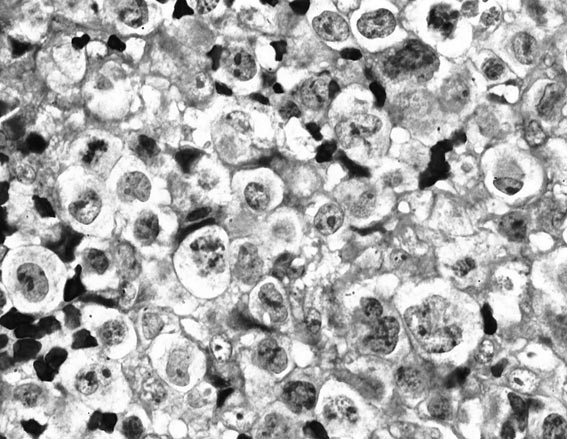

A 6.0 × 6.0-cm fungating mass involved the left breast with extensive epidermal necrosis. The cells infiltrating the tissue were large and monomorphic with focal areas of myxoid change in the background (Fig. 1). Rare Hodgkin's-like cells were present. Necrosis and inflammation were extensive. The cells were immunoreactive with CD45RB, CD30, CD45RO, CD43, ALK-1, TIA-1, epithelial membrane antigen, and βF1 (Fig. 2). CD3 was focally immunoreactive. CD20 and CD56 were negative. The malignant lymphoma was within the breast tissue near the epithelium, but cytokeratin did not show a lymphoepithelial (LE) component. The molecular genetic IgH assay was nonamplifiable. TCR β and γ assays showed a monoclonal band.